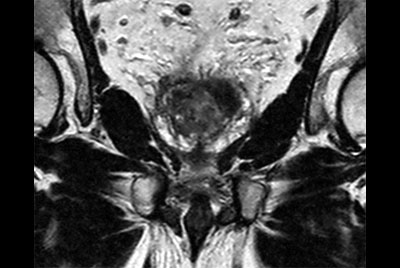

Prostate with dual coil set-up

Multi-phase, contrast-enhanced prostate imaging

Prostate with Vega HP gradients

Compressed SENSE Prostate imaging

Prostate with dS ZOOM imaging

High resolution Prostate imaging with Compressed SENSE

Prostate lesion with fat-free mDIXON XD imaging

Prostate lesion with high b-value DWI

Prostate imaging with motion reduction techniques

Prostate with Compressed SENSE on BlueSeal magnet

MR-only simulation prostate

MRI simulation for prostate cancer treatment

Prostate imaging with dS Endo + dS Torso coil

Prostate imaging

Multi-parametric MR of the prostate

Prostate with the dS Torso coil at 1.5T

Prostate Biopsy

Prostate with the dS Endo coil

Prostate with the dS Torso coil at 3.0T